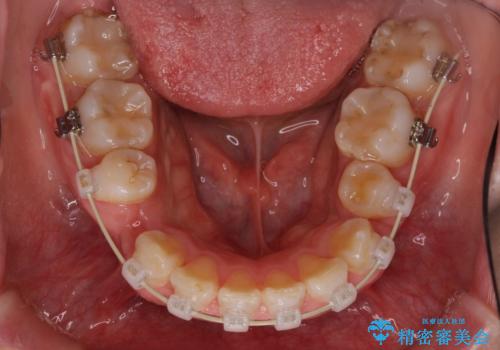

- ガタガタと出っ歯を主訴に来院されました。

上下左右の歯を1本ずつ、合計4本抜歯してワイヤーにて矯正治療をすることとなりました。

前から4番目の歯を抜歯することが多いのですが、右上の前から5番目の歯が神経の治療済みであり、こちらの歯を抜歯する計画としました。

通常より治療期間を要しましたが、健康な歯を残すことができました。